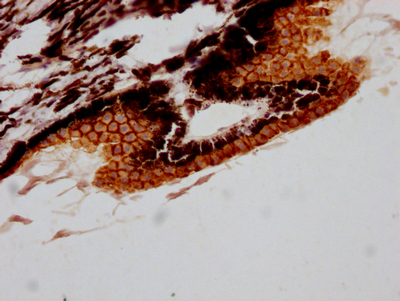

IHC image of CSB-RA212530A0HU diluted at 1:100 and staining in paraffin-embedded human eye tissue performed on a Leica BondTM system. After dewaxing and hydration, antigen retrieval was mediated by high pressure in a citrate buffer (pH 6.0). Section was blocked with 10% normal goat serum 30min at RT. Then primary antibody (1% BSA) was incubated at 4℃ overnight. The primary is detected by a Goat anti-rabbit IgG polymer labeled by HRP and visualized using 0.05% DAB.

產品描述:CSB-RA212530A0HU RPE65重組單克隆抗體是針對視網膜色素上皮特異性蛋白RPE65開發的高特異性科研工具,該靶點在視覺循環中催化全反式視黃酯轉化為11-順式視黃醇,是維持正常視覺功能的關鍵酶。經嚴格驗證,本抗體在ELISA和免疫組化(IHC)實驗中表現出優異性能,推薦IHC使用稀釋比為1:50-1:200,可在人視網膜組織樣本中精準定位RPE65蛋白表達。其重組單克隆特性確保了批次間的高度一致性,適用于視網膜病變機制研究、基因治療載體表達效率評估以及維生素A代謝相關信號通路探索等科研領域。實驗數據表明,該抗體能清晰顯示視網膜色素上皮層的特異性染色模式,為研究年齡相關性黃斑變性、萊伯先天性黑蒙等遺傳性眼病提供了可靠工具,同時也可用于體外模型中視黃醇代謝調控的分子機制解析。